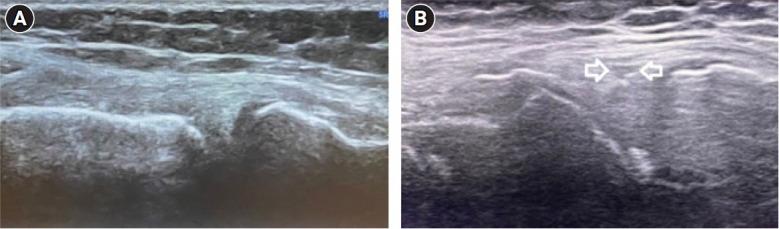

Musculoskeletal ultrasound is increasingly used as the modality of choice in diagnosing many medical situations. The present study aimed to compare the accuracy of point-of-care ultrasonography (POCUS) and magnetic resonance imaging (MRI) to detect acute medial meniscus tears in knee.

METHODS

The prospective study was conducted on patients with suspected medial meniscus tears in knee. in the emergency department. In the absence of a knee fracture on x-ray, POCUS on the knee was performed. All patients underwent POCUS and MRI of the knee followed by arthroscopy. POCUS findings were then compared to MRI findings to diagnose medial meniscus tears.

肌肉骨骼超声在许多医疗情况的诊断中越来越多地被用作首选方式。本研究旨在比较床旁超声检查(POCUS)和磁共振成像(MRI)检测膝关节急性内侧半月板撕裂的准确性。

方法

对急诊科疑似膝关节内侧半月板撕裂的患者进行前瞻性研究。在X线检查未发现膝关节骨折的情况下,对膝关节进行POCUS检查。所有患者均接受膝关节的POCUS和MRI检查,随后进行关节镜检查。然后将POCUS检查结果与MRI检查结果进行比较,以诊断内侧半月板撕裂。